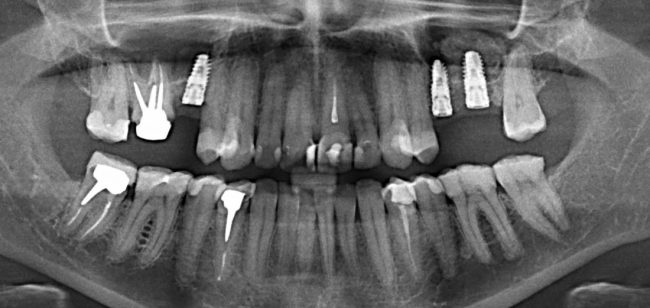

После операции:

— контрольный снимок (раньше делали ОПТГ, сейчас — строго КЛКТ)

Для этого мы сделали КЛКТ:

И КЛКТ показала нам, что с имплантатами и окружающей костью всё зашибись. Через 12 лет после операции, отсутствия наблюдения, пофигизма в замене временных коронок! Нужны ли тебе еще какие-нибудь доводы в пользу долгосрочной эффективности метода?

Серия контрольных снимков на этапах: